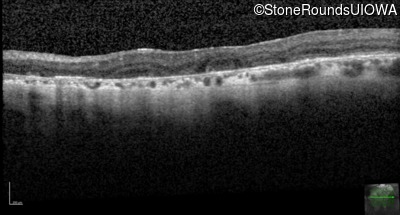

Optical Coherence Tomography - Left - 20/200

Exemplar / OCT Stack